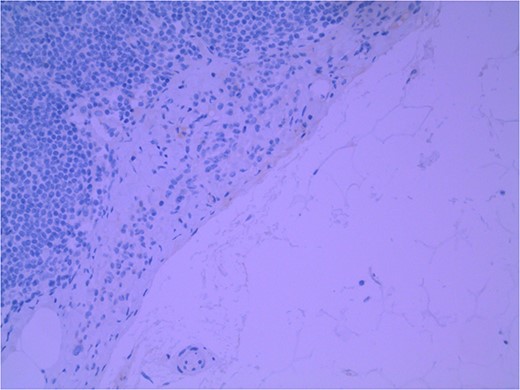

Lymph node specimens were sent for haematoxylin and eosin (H&E) staining (Fig. 3) and IHC analysis. The sections showed mild reactive changes and benign intracapsular nevoid rests. IHC analysis showed that these cells were negative for HMB-45 (Fig. 4) and were positive for both Sox10 and p16 (Figs 5 and 6). Consensus at the Multidisciplinary Team Meeting was that the appearance was in keeping with benign naevoid rests as opposed to melanoma deposits, given the location of the cells, morphology and immunohistochemistry. Surveillance was recommended.

Lymph node; nevoid melanocytes in subcapsular region; H&E × 200 magnification.